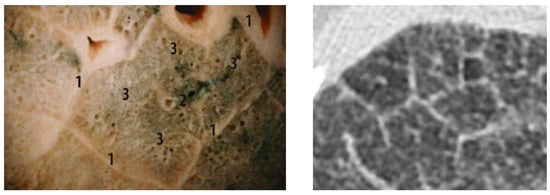

A comparison of the obtained images after improvements/filtering (see Figure 9) with the lung lobulus anatomy is shown in Figure 10, where the left image represents a cadaver section and the right one a high-resolution computer tomography (HRCT) image. It is quite obvious that we managed to achieve a completely adequate imaging method that makes the lung tissue visible in an excellent way.

Figure 10. Lung lobulus anatomy: a cadaver section of the lungs with visible lung lobules with 1 for interlobular septa, 2 for central bronchioles, and 3 for alveolar region (left); an HRCT section of the patient with interstitial edema, where the septa and lobules are clearly visible (right) [48].